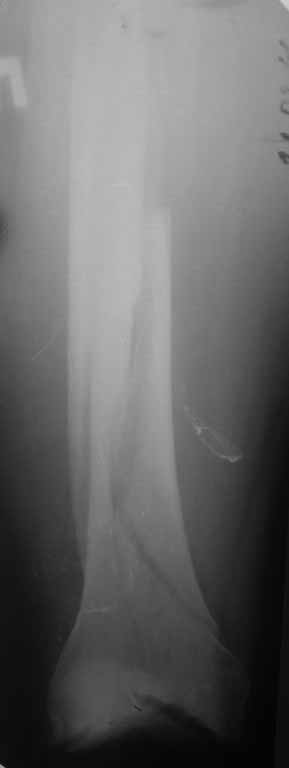

Представляю вам один из наших недавних случаев выполнения малоинвазивного остеосинтеза бедренной кости обычной пластиной 95 градусов. Длина восстановлена с помощью дистрактора (по сути это основная и б(о)льшая часть репозиции). Произведено два небольших доступа, проведена спица направитель. Рентген-контроль для подтверждения достаточной длины/оси (ЭОП использовался в другой операционной). Создание туннеля обратной стороной фиксатора. Поворот фиксатора, введение клинка по спице. Фиксация проксимального и дистального концов пластины.